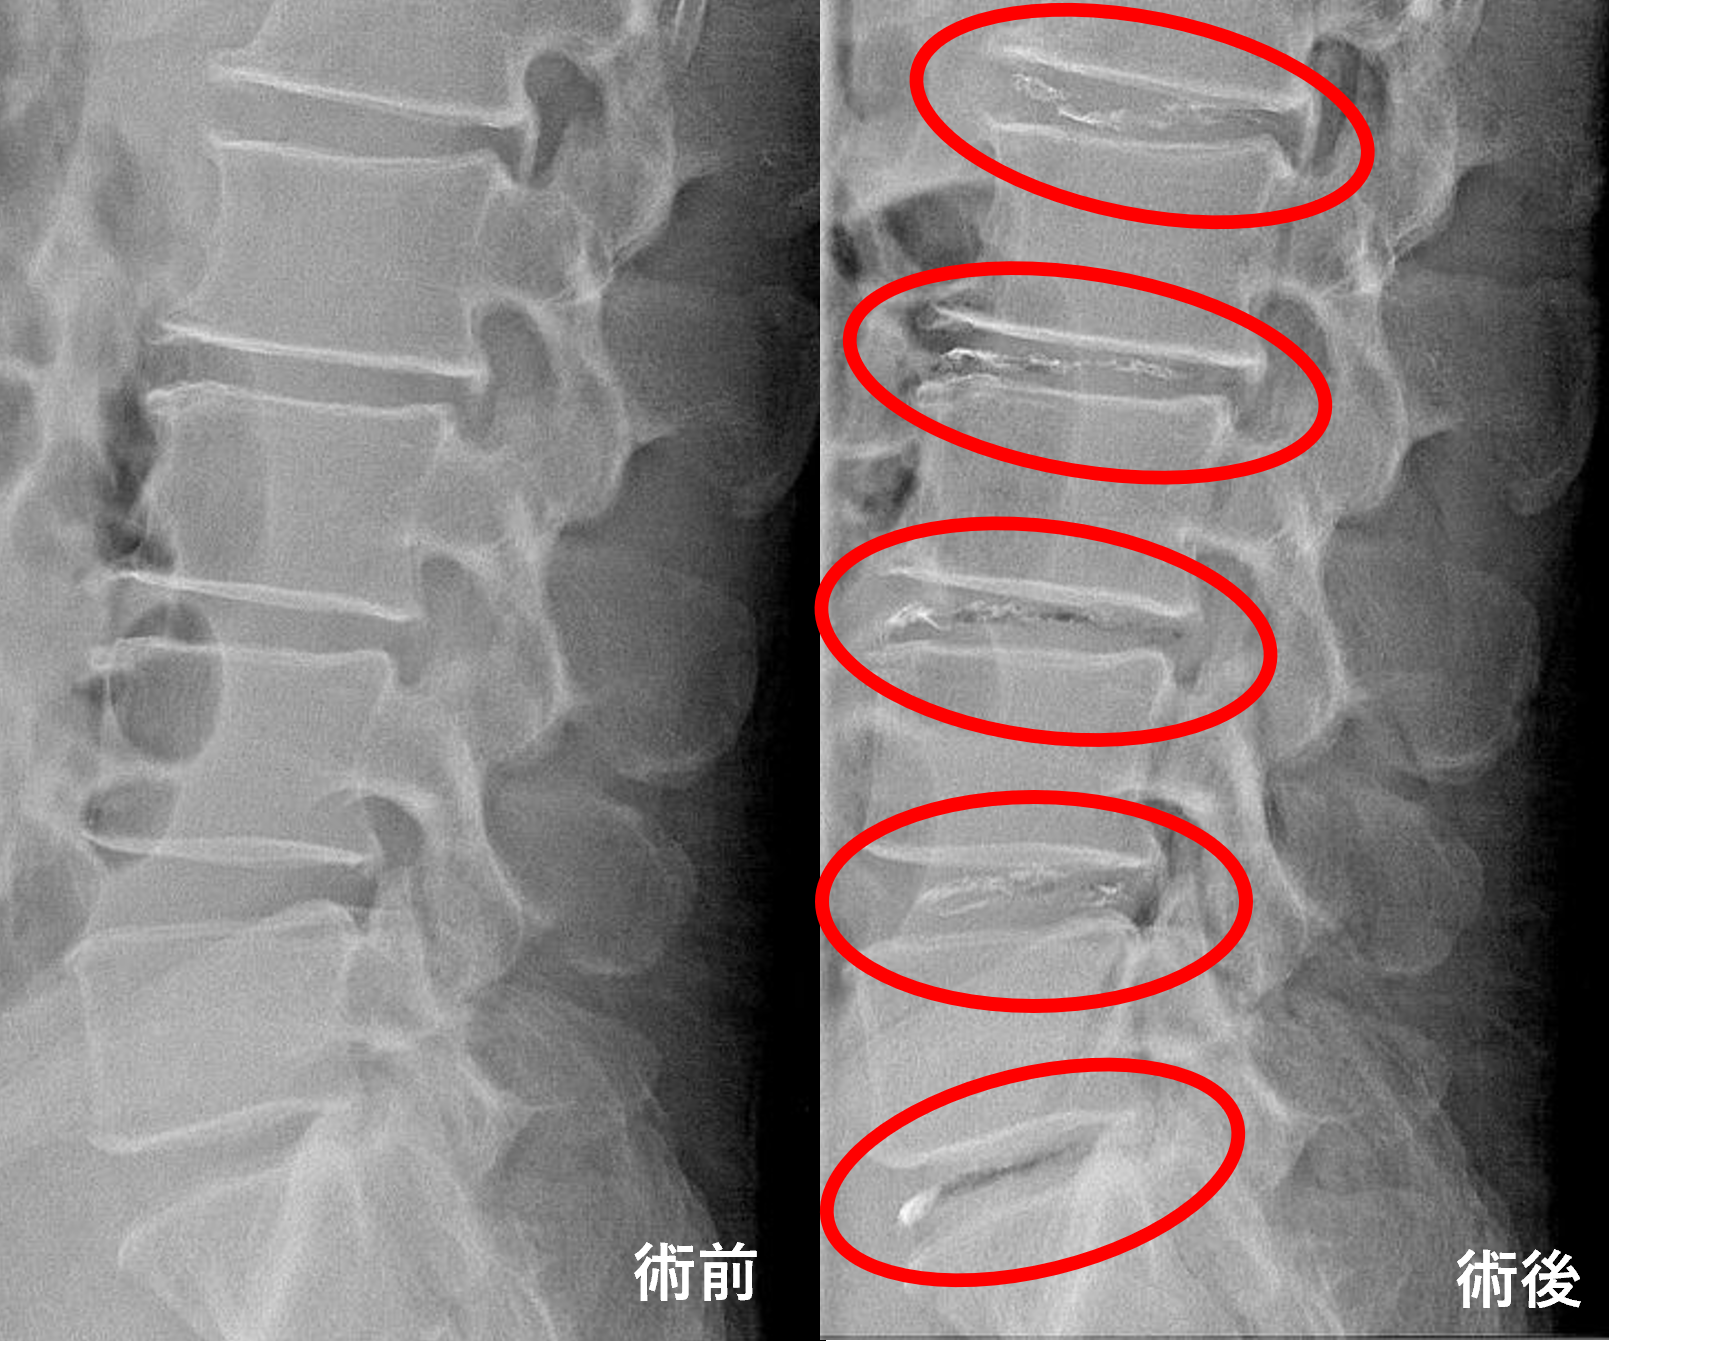

画像及び所見について

- L1/2、2/3、3/4、4/5、5/s – 椎間板変性、椎間板ヘルニア

以上のことが画像上認められました。

L1/2、2/3、3/4、4/5、5/sの椎間板所見による脊柱管の圧排が、原因の可能性が高い。

患者様と相談の元、L1/2、2/3、3/4、4/5、5/sにセルゲル法を施行